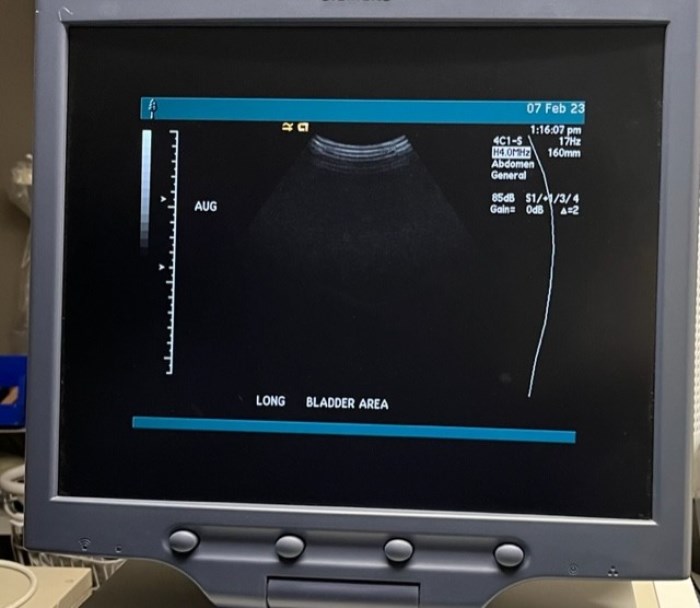

Siemens Sequioa Ultrasound

Pre-owned. In good working condition. Shown as is. Siemens Sequoia Ultrasound. DOM: 2006

Probes: 15L8w, 4V1, 10V4, 6L3, 4C1